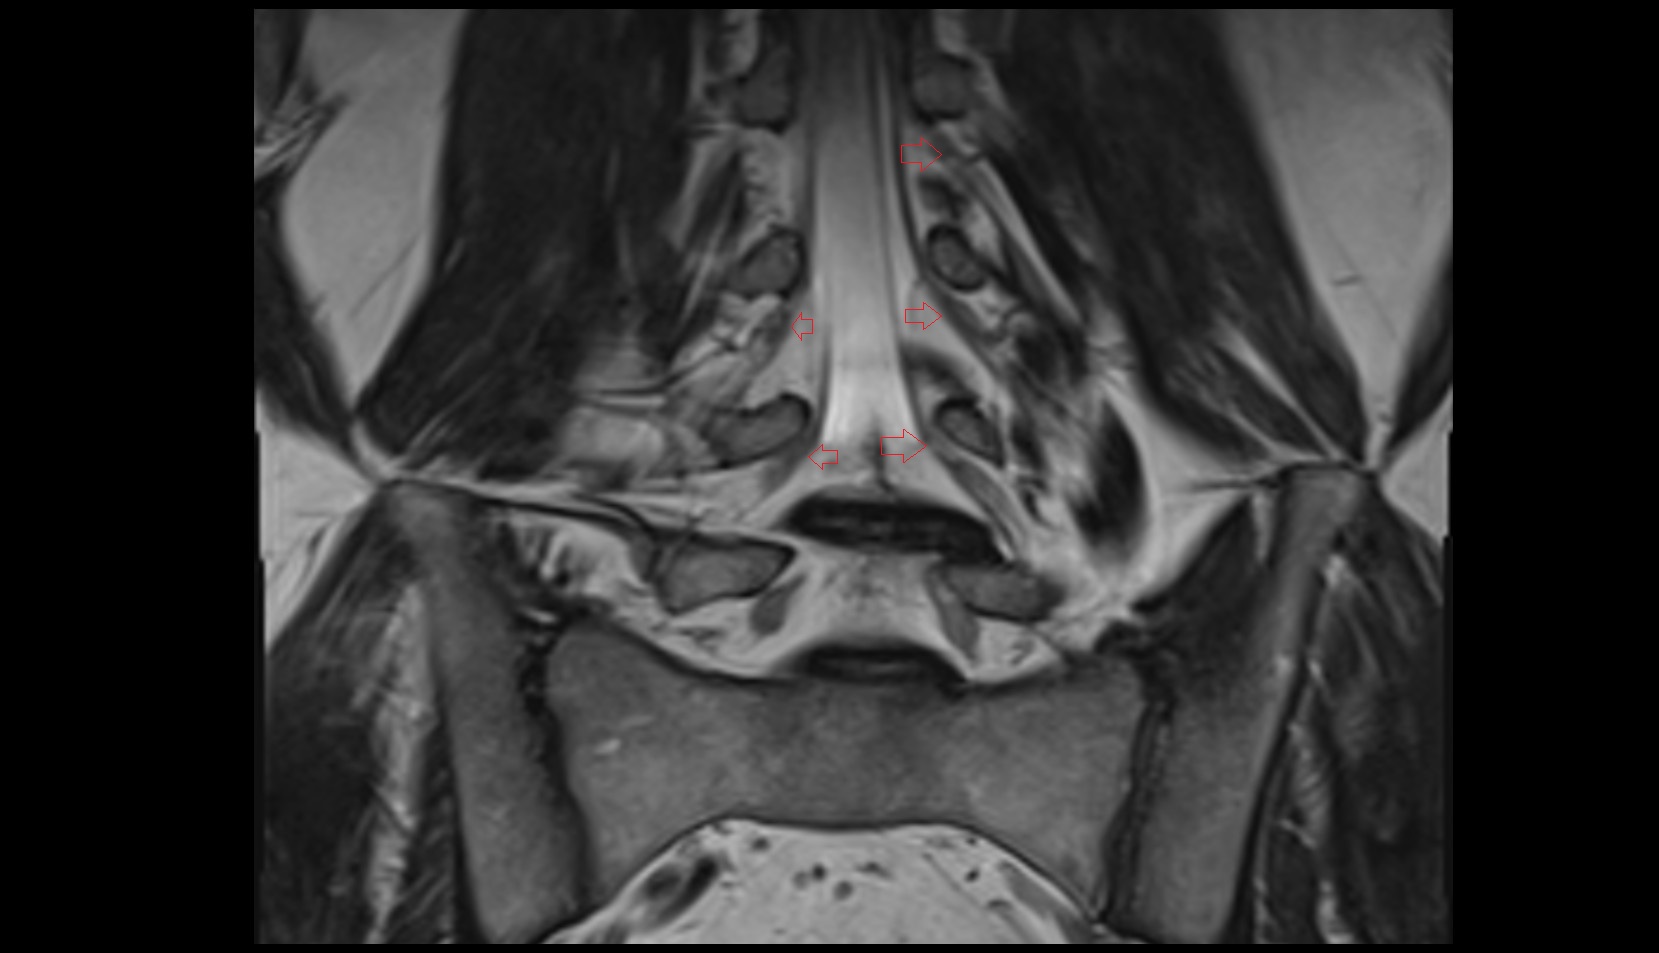

- Traversing nerve root of spinal nerve

- Exiting nerve root of spinal nerve

- Dorsal traversing nerve root

- Ventral traversing nerve root

- Dorsal exiting nerve root

- Ventral exiting nerve root

- Dorsal root ganglion of spinal nerve